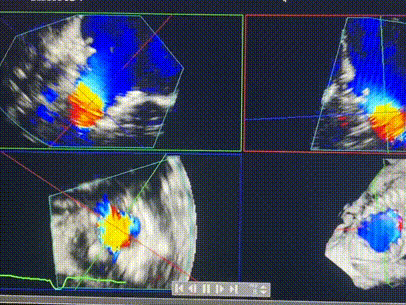

術前超聲提示重度三尖瓣反流

接受本次LuX-Valve Plus治療的是一位三尖瓣重度反流的高齡女性,患者早前曾由于二尖瓣疾病行經導管二尖瓣置換術,植入Tendyne瓣膜一枚,且有ICD植入史。術前CT分析結果顯示,瓣環大小為47.6mm,血管無明顯迂曲和鈣化。由于患者三尖瓣解剖結構復雜,二尖瓣位人工瓣膜造成的超聲偽影和ICD導線的干擾使得歐洲沒有其他合適的商業化和臨床試驗的產品可以對其進行治療。經過Rodrigo Estévez-Loureiro教授團隊的詳盡術前評估,認為LuX-Valve Plus經導管三尖瓣置換系統可以對該患者進行有效的治療。因此,Rodrigo Estévez-Loureiro教授團隊最終決定使用這一中國創新器械為患者進行手術。法國波爾多里爾大學附屬醫院的Thomas Modine教授與加拿大圣保羅醫院的Anson Cheung教授全程線下指導本次手術。